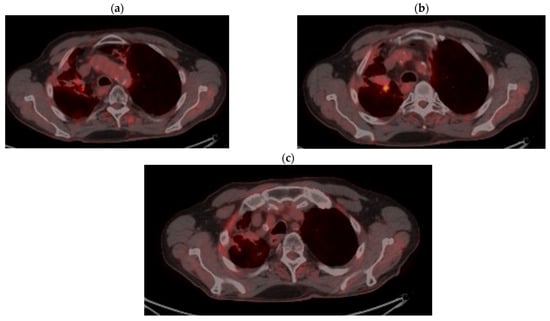

2. Case Presentation

2.1. Systemic Third-Line Therapy (4xDocetaxel) Was Initiated 04–07/2020

2.2. Monitoring 2022: Oncological Commission 1910/16.08.2022

2.3. Oncological Committee 07/25/2023 Recommended